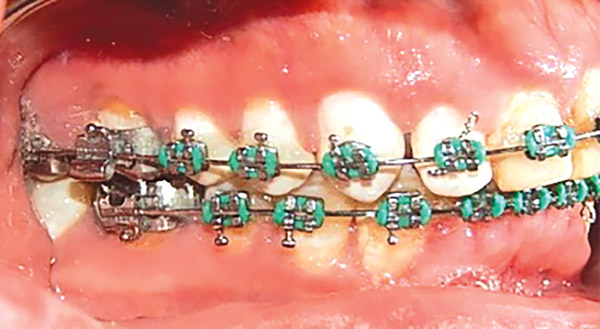

Estudios de progreso

Se observa en las fotografías intraorales la mecánica utilizada con los brackets y al paciente con mejor alineación y nivelación dental (Figura 12-14).

Figura 12. Intraoral derecha.

Figura 13. Frente.

Figura 14. Izquierda.

Respecto a las formas de arco superior e inferior que eran cuadradas en esta fase ya son ovales (Figura 15 y 16).